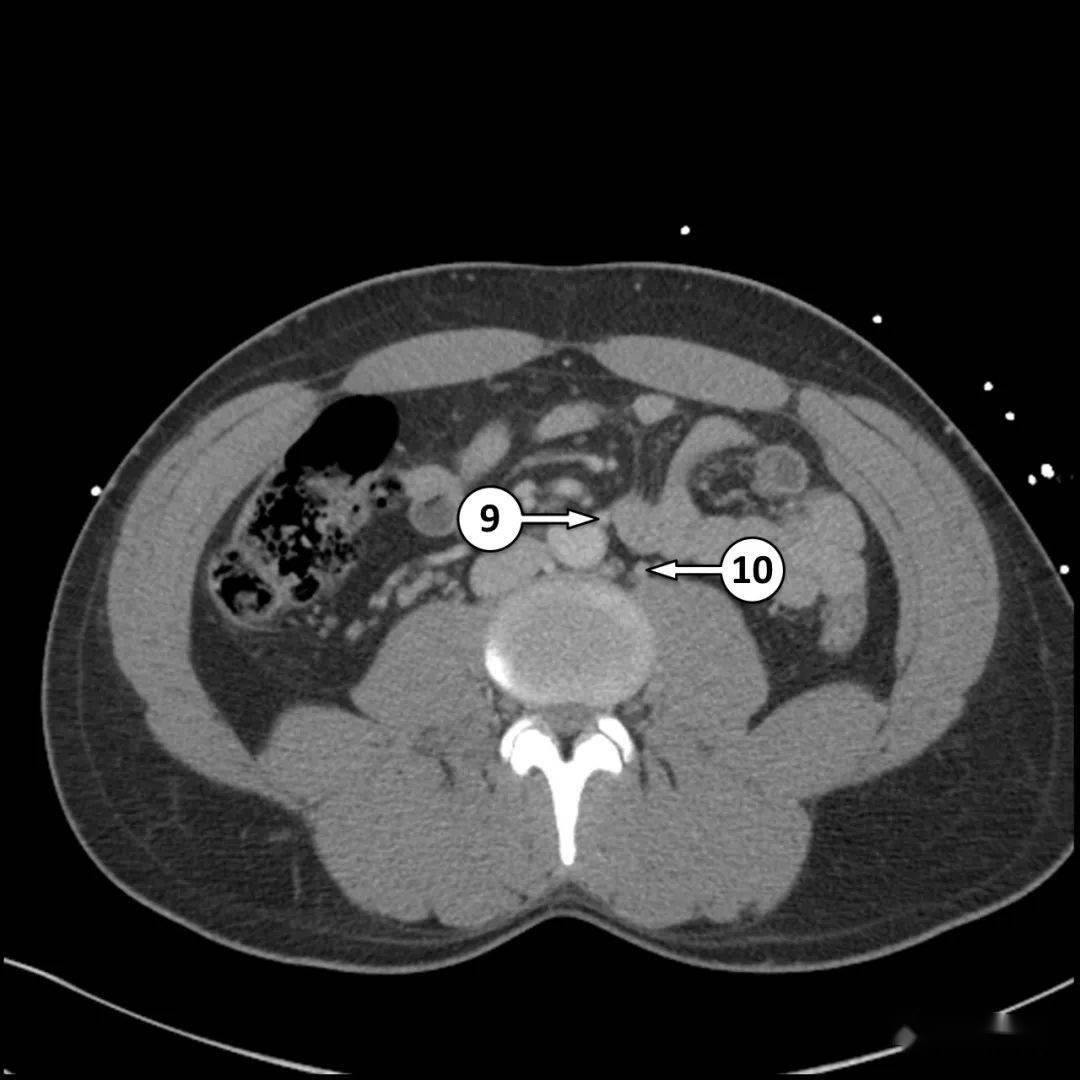

半月线4.性腺血管3.

居正中的是腹白线,两侧的分别为半月线

5分钟看完这篇,学会全腹ct解剖_动脉_静脉_血管